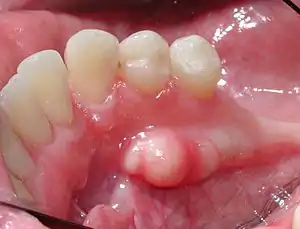

| Mandibular torus in premolar area | |

Torus mandibularis is a bony growth in the mandible along the surface nearest to the tongue. Mandibular tori are usually present near the premolars and above the location of the mylohyoid muscle's attachment to the mandible.[1] In 90% of cases, there is a torus on both the left and right sides.